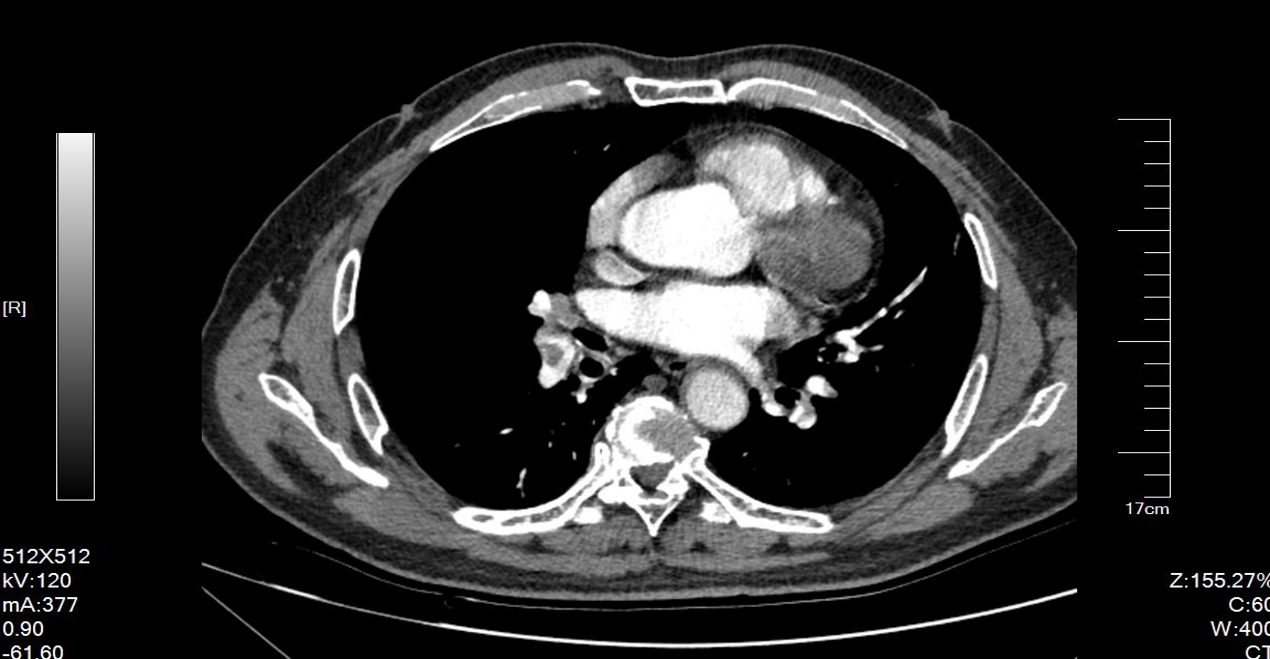

2023-12-08 行泌尿系增强CT:左肾肿物,考虑肾癌,累及左侧肾盂。下腔静脉,左肾静脉长条状充盈缺损,考虑瘤栓。

2023-12-08 肺CTPA:左右两肺动脉主干,两肺各叶动脉及部分段分支内见低密度充盈缺损。

初步诊断:左肾恶性肿瘤(T3bNxM1),下腔静脉瘤栓(Ⅱ级)(越过第一肝门水平),肺栓塞(瘤栓)

2024-04-03 复查泌尿系增强CT:左肾肿物较治疗前稍缩小,腔静脉瘤栓高度无明显下降。

2024-03 复查肺CTPA:主肺动脉增宽,左右肺动脉主干及大部分分之内可见低密度充盈缺损。考虑双侧大面积中央为主型急性肺动脉栓塞。

2024-10复查泌尿系增强CT:左肾肿物较治疗前明显缩小,腔静脉瘤栓高度将至第一肝门以下。